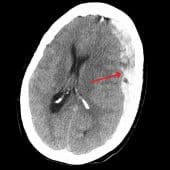

Ежегодно в России регистрируется около 600 тысяч случаев черепно-мозговых травм, причем до 40% всех внутричерепных кровоизлияний составляют субдуральные гематомы. Это опасное состояние, возникающее при разрыве сосудов между мозгом и черепом, приводит к сдавлению мозга и требует экстренного выбора лечения — консервативного или хирургического. Особую тревогу вызывает высокая летальность при обширных субдуральных гематомах, а также риск повторных кровоизлияний, с которыми сталкивается каждый третий пациент, принимающий препараты для разжижения крови. Ученые ПГМУ им. академика Е.А. Вагнера и ПНИПУ создали и запатентовали компьютерную программу, прогнозирующую перспективы лечения. В основу алгоритма легли клинические исследования, позволившие выделить ключевые прогностические факторы: возраст пациента и расположение гематомы. Система анализирует и другие параметры — объем кровоизлияния, время до госпитализации и прием антикоагулянтов. Разработка поможет врачам не только выбирать оптимальную тактику лечения, но и объективно оценивать шансы пациента на восстановление.